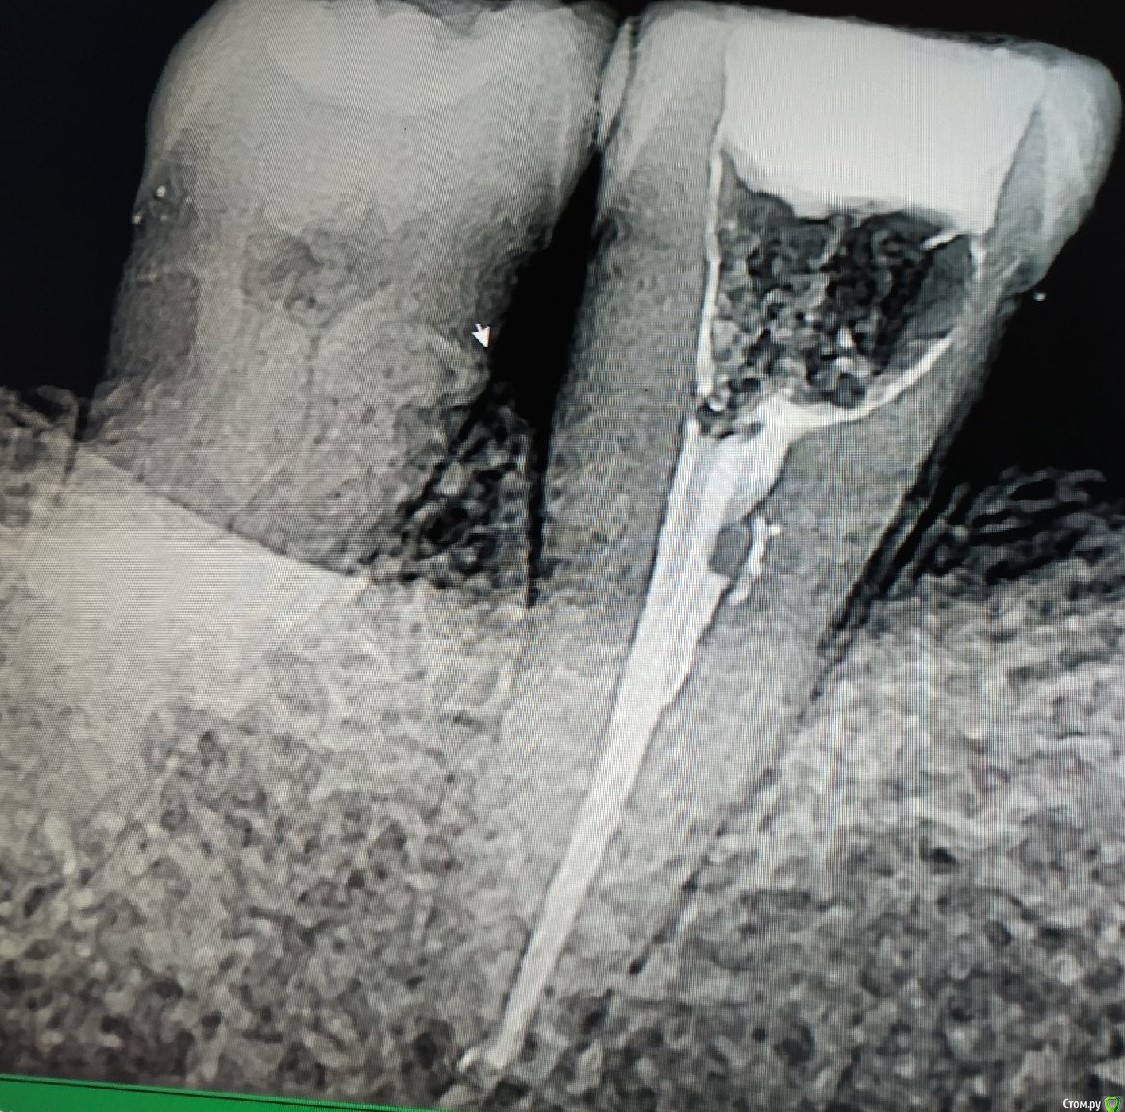

Кейс под названием: Что для тебя успешное эндо?

Пациент: девушка 16 лет. Задача дотянуть зуб сколько сможем по времени, затем имплантация.

Исходная ситуация:  симптоматический апикальный периодонтит. Отломок в медиально-щечном канале.IMG_20210716_134030.thumb.jpg.0b754f1cf44f10a3d2e05ed70884f5b7.jpg

Бился примерно 2 часа, Прошел медиально-язычный. Немного обошел обломок, за ним стопорюсь. Дистальный глухо. Оставил пульпосептин, готовился к удалению.

На следующем приеме жалоб нет, принял решение пломбировать что есть.

С пацом решили: если за 3 месяца не появится болей, и в прицельном не появится разряжение - то коронуем.

3 месяца спустя:

Устанавливаем коронку.

Прошло 1.5 года.

Звонит: ходуном ходит зуб. Думаю: ну, здравствуй, обострение, здравствуй, удаление. Пришла, оказывается расцементировка коронки. Делаем снимок:

IMG_20210716_134216.thumb.jpg.209b4330c838774d9bf6e170ae51304f.jpg